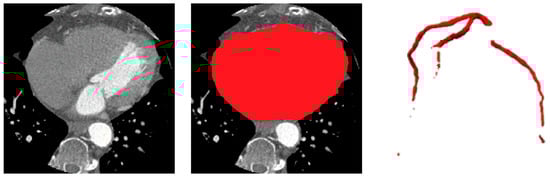

The vesselness-enhanced inputs allow the ASOCA-trained ResU-Net to delineate coronary arteries more accurately, even in regions with low contrast-to-noise ratio. When applied to the gated COCA CT scans—cropped to the heart ROI—the resulting vessel masks serve as anatomical constraints for the downstream calcification segmentation stage. These vessel priors ensure that detected lesions are spatially restricted to plausible coronary regions, reducing false positives near the aorta, valves, or pericardium and improving the sensitivity and specificity of calcification segmentation. Examples of the heart and coronary arteries segmentations are shown in Figure 4.

Figure 5 illustrates qualitative example of the heart and vessel segmentation results. The heart ROI masks generated by the ResU-Net trained on MM-WHS successfully isolate the cardiac region from surrounding thoracic structures. The vessel segmentation obtained from the ASOCA-trained ResU-Net clearly delineates major coronary branches, while the overlay image demonstrates precise spatial alignment of the coronary arteries within the extracted heart ROI. This confirms the anatomical plausibility and structural integrity of the upstream stages, which serve as essential priors for vessel-aware calcification segmentation in the subsequent stage.

Figure 4. Heart and Coronary Vessel Segmentation: original CT slice, predicted heart region of interest (ROI) and 3D coronary artery segmentations.

Figure 5. Qualitative results of heart and vessel segmentation. From left to right: original CT slice, heart segmentation, extracted heart ROI, coronary vessel segmentation, and 3D rendering of coronary vessels.